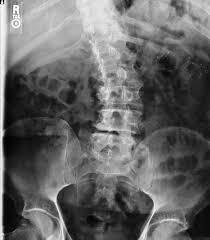

To get the hips level we first have to know how unlevel they are. Go to a chiropractor and get a set of standing x-rays. These are taken under the effects of gravity. Only chiropractors take standing x-rays. Chiropractors understand the relationship of structure vs. function.

Can you see how unblevel hips throws you out of balance?

The correction is easy. I take accurate measurements on how unlevel the hips are. I will need to put a heel insert inside the shoe to correct this. Sorry – not everybody is level. I even have to have a heel lift in my left shoe.